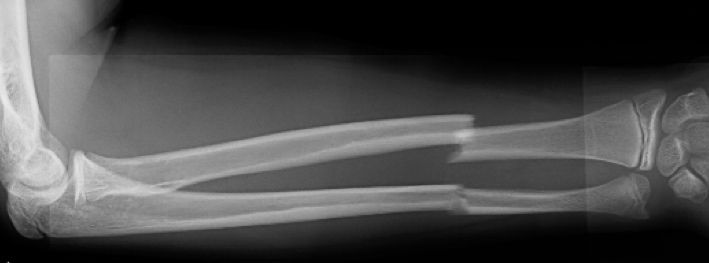

Las fracturas de ambos huesos del antebrazo al mismo nivel, con líneas de fractura oblicua-transversa o desplazamiento convergente son inestables y precisarán de tratamiento quirúrgico. En estos casos está indicado, dependiendo de la edad del paciente, el tratamiento mediante reducción y osteosíntesis. El enclavado intramedular elástico es el tratamiento de elección (Figura 15).

Figura 15: a-Imagen clínica de fractura de antebrazo derecho con gran deformidad. b- Radiografía donde se aprecia fractura de radio-cúbito de trazo transverso en el mismo nivel. c, d-Enclavado intramedular elástico. e,f- Imagen final con buena consolidación ósea.